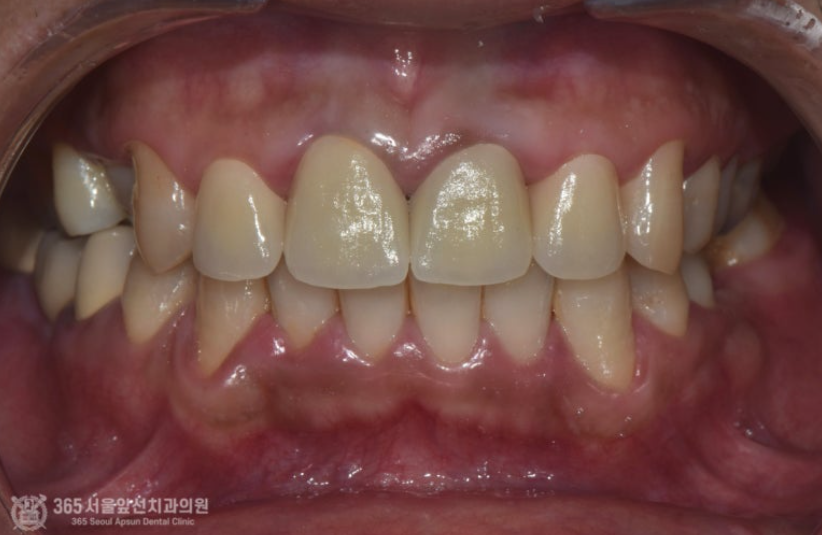

위쪽 앞니 보철물을 한지 오래됐는데, 바꾸고 싶어요. 안녕하세요. 주안역치과 365서울앞선치과 대표원장 강동우입니다. 오늘 소개해드릴 치료 증례는 앞니 보철물이 어색하다는 불편감으로 내원하신 환자분의 증례입니다~ 앞니는 치아의 기능도 중요하지만 무엇보다 심미성이 중요합니다. 쉽게 말해 앞니는 이쁜게 중요하다고 볼 수 있습니다 ㅎㅎ 촬영일시 : 2024.05.03. 처음 내원 당시 정면 모습입니다. 환자분께서 나이가 젊으셨음에도 불구하고 앞니의 보철물의 색상이 탁하고 어두워보이며 심지어 앞니 끝부분이 깨져있는것도 보입니다. 또한 PFM이라고 내부에 금속구조물을 포함한 보철물이다보니 금속 구조물이 빛의 투과를 막아 잇몸색이 탁한 색으로 보이는 우산효과(umbrella effect)도 관찰됩니다. 촬영일시 : 2024.05.03. 내원 당시 치료전 엑스레이입니다. PFM으로 제작된 앞니 보철물이 관찰되며, 치아 내부에 신경치료가 행해졌던 흔적도 보입니다. 환자분께서 증상은 따로 없으셨으나, 신경치료 상태가 불량하여 재신경치료도 진행하기로 했습니다. 촬영일시 : 2024.05.03. 재신경치료 중에 촬영한 엑스레이입니다. 정확하게 신경치료가 이루어지고있는것이 관찰됩니다. 촬영일시 : 2024.05.03. 재신경치료 후 엑스레이 사진입니다. 깔끔하게 충전된 양상이 관찰됩니다. 촬영일시 : 2024.05.03. / 2025.08.02. 이제 심미의 완성을 위한 잠정보철물(Provisional restoration)을 제작하여 환자분께서 원하는 형태를 찾아가며, 잇몸의 형태도 조절하는 과정(gingival molding)을 진행합니다. 환자분께서 심미를 중요시 여기는 분이셔서 두 번에 걸친 임시치아 제작 단계를 거쳐 최종적인 보철물을 만들었습니다. 촬영일시 : 2025.08.02. 완성된 최종보철물입니다. 깔끔하게 잘나왔습니다 어두웠던 잇몸색상도 개선되었습니다. 환자분께서도 만족하셨습니다 ㅎㅎ 촬영일시 : 2024.05.03. / 2025.08.02. 치료 전후 비교 모습입니다. 드라마틱한 변화가 관찰됩니다. 오늘은 오래된 앞니 보철물 교체에 관한 주제로 증례를 소개해드렸습니다. 앞으로도 좋은 치료로 보답하는 석바위시장치과, 365서울앞선치과가 되겠습니다 ! [ 치료기간: 2024년 5월3일 ~2025년 8월 2일 ] ※ 365서울앞선치과의원의 모든 포스팅은 각 진료과 의료진이 직접 작성합니다. 365서울앞선치과의원 블로그의 임상 케이스 게시물은 환자분께 의학적으로 정확하고 상세한 정보를 드리기 위해 각 진료과 의료진이 직접 작성하며, 모든 증례 사진은 본원 의료진이 직접 시술한 증례를 촬영한 것으로, 의료법 제23조, 제56조에 의거하며 환자분의 동의를 얻어 포스팅에 사용하였습니다. 또한 해당 케이스는 본 환자분의 치료 결과이며, 환자 상태에 따라 치료의 결과는 달라질 수 있습니다. |